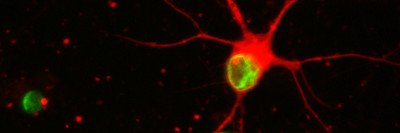

Human Stem Cells Treat Parkinson’s in Mice

New research published in Nature by Sloan Kettering Institute developmental biologist Lorenz Studer describes how stem cells from human embryos were us...